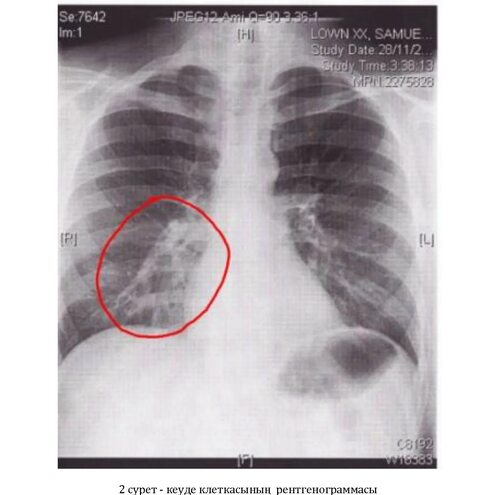

Бронхит – это распространенное воспалительное заболевание дыхательных путей, которое может вызвать различные симптомы и изменения в легких. Для диагностики бронхита может использоваться рентгеновский снимок легких, позволяющий визуально увидеть характерные признаки заболевания.

На рентгеновском снимке легких при бронхите можно обнаружить следующие изменения:

- Увеличение размеров бронхов;

- Отек слизистой оболочки бронхов;

- Наличие слизи и мокроты в бронхах;

- Повышение плотности легочной ткани;

- Неоднородность распределения воздуха в легких.

Эти изменения могут быть видны на рентгеновском снимке в виде темных областей, утолщений или размытости контуров.